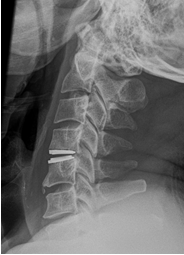

2. Posterior Neck Surgery in a 68 year old following a fall, causing a neck fracture-dislocation at C4/5 and C7.

The post-operative X-rays were taken at 3 months after the incident.